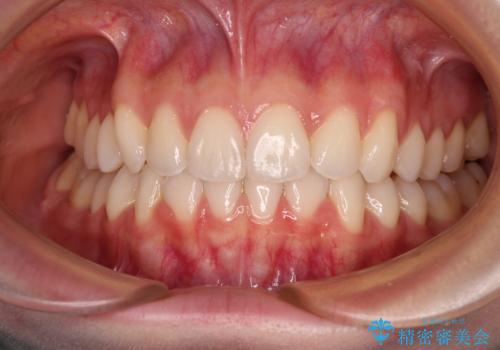

矯正治療中は汚れが溜まりやすく、歯肉からの出血が続きましたが、最終的には歯を保存して安定した状態で補綴治療を行うことができました。